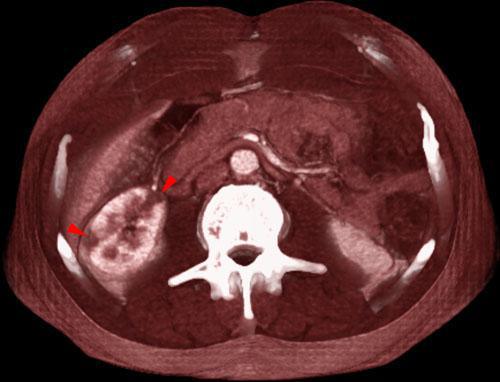

La obstrucción unilateral de una arteria renal puede dar lugar a un cuadro isquémico agudo o una atrofia renal por isquemia crónica.

Su estudio debe realizarse mediante ecografía y fundamentalmente mediante AngioTC que nos permite localizar el lugar de la oclusión reservando la angiografía por sustracción digital para los tratamientos endovasculares oportunos.